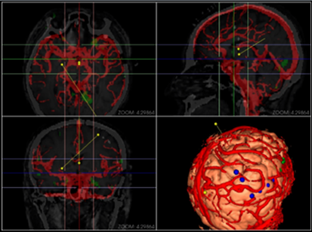

同方鼎欣專業(yè)影像產(chǎn)品群是直接面向神經(jīng)外科、骨科、血管分析等臨床科室的輔助診療、手術(shù)計劃、分析的解決方案,系統(tǒng)整合了醫(yī)療影像的導(dǎo)入、二維閱片、三維重建、序列配準(zhǔn)融合、自動分割、自動計算、手術(shù)計劃等一系列功能。充分滿足了臨床科室的專業(yè)需求,提供了完整、強(qiáng)大、可靠、方便的工具平臺。

三維體繪制重建(VR)、三維面繪制重建(SR);

融合(Fusion)、融合結(jié)果三維重建;

神經(jīng)外科手術(shù)規(guī)劃模塊;

心腦血管分析模塊